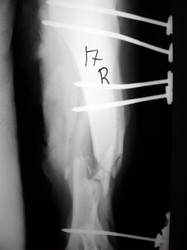

PRÁCTICAS CURSO DE FIJACIÓN EXTERNA PERFECCIONAMIENTO.

Húmero.